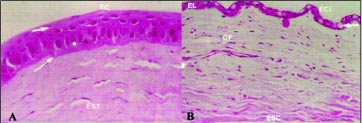

Descrição dos cortes histológicos no 28º dia

O epitélio que recobriu a córnea manteve as mesmas características já mencionadas para o momento precedente nos três grupos. Chamou atenção a presença de células caliciformes que, nesse momento, se encontraram com densidade máxima nas três técnicas (Fig. 7). Estiveram presentes em todas as re giões da superfície ocular, desde o epitélio conjuntival, passando pelo epitélio límbico, até nas áreas centrais do epitélio que recobriu a córnea. A densidade das células comportou-se como já mencionado: cerca de 12 células/campo de maior aumento (400X) no limbo e nas regiões periféricas do epitélio da córnea e cerca de 6 células/campo no centro. Além da característica irregularidade da espessura do novo epitélio, perceberam-se, também, algumas falhas (pontos de ausência de epitélio), provavelmente correspondentes às lesões puntatas observadas clinicamente, com menos freqüência em T1, intermediárias em T2 e mais freqüentes em T3.

A inflamação regrediu em relação ao momento precedente na T1(Fig. 7A,B), enquanto na T2 e T3 atingiu seu pico máximo (Fig. 7C). O edema corneano e o infiltrado de células inflamatórias ausentes ou discretos na T1, moderados ou intensos na T2 e T3, estando, nestes casos, situados apenas no terço estromal mais superficial (Fig. 7A,C).

A vascularização corneana progrediu algo mais; sem atingir, no entanto, a região central da córnea na T1, sendo percebida na maior parte dos cortes histológicos (quadrantes), atingindo o centro da córnea na T2 e T3. Com a redução do edema, tornou-se mais superficial, localizando-se apenas no terço superficial.

A resposta fibroblástica acompanhou a proliferação vascular, ultrapassou a região límbica, sendo percebida também na região periférica da córnea na T1. Na T2, foi mais visível na região periférica, tornando-se esparsa à medida que se aproximou da região central. Na T3, foi percebida, algumas vezes, até mesmo junto aos vasos mais centrais.

Descrição dos cortes histológicos no 56º dia

O padrão do epitélio que recobriu a córnea se manteve similar aos encontrados nos dois momentos anteriores, porém, embora tenha havido uma redução significativa em sua densidade, as células caliciformes continuaram presentes nas três técnicas.

Nas três técnicas, o infiltrado inflamatório persistiu, porém, em menor intensidade, principalmente nas proximidades dos vasos. Observaram-se células inflamatórias, predominantemente mononucleares, nas proximidades dos vasos. O edema foi mínimo ou ausente.

A vascularização foi percebida, permeando o estroma superficial, logo abaixo do epitélio. Atingiu até a região paracentral na T1, até a região central na T2 e T3.

A resposta fibroblástica que acompanhou os vasos também foi percebida, atingindo até a região paracentral na T1, atingindo até a região central na T2 e T3.

Nas três técnicas, a resposta fibroblástica reparativa e a proliferação vascular permearam no terço estromal superficial, sem, contudo, haver evidência histológica da formação de tecido fibro-escleroso denso ou cicatriz propriamente dita (Fig. 8).